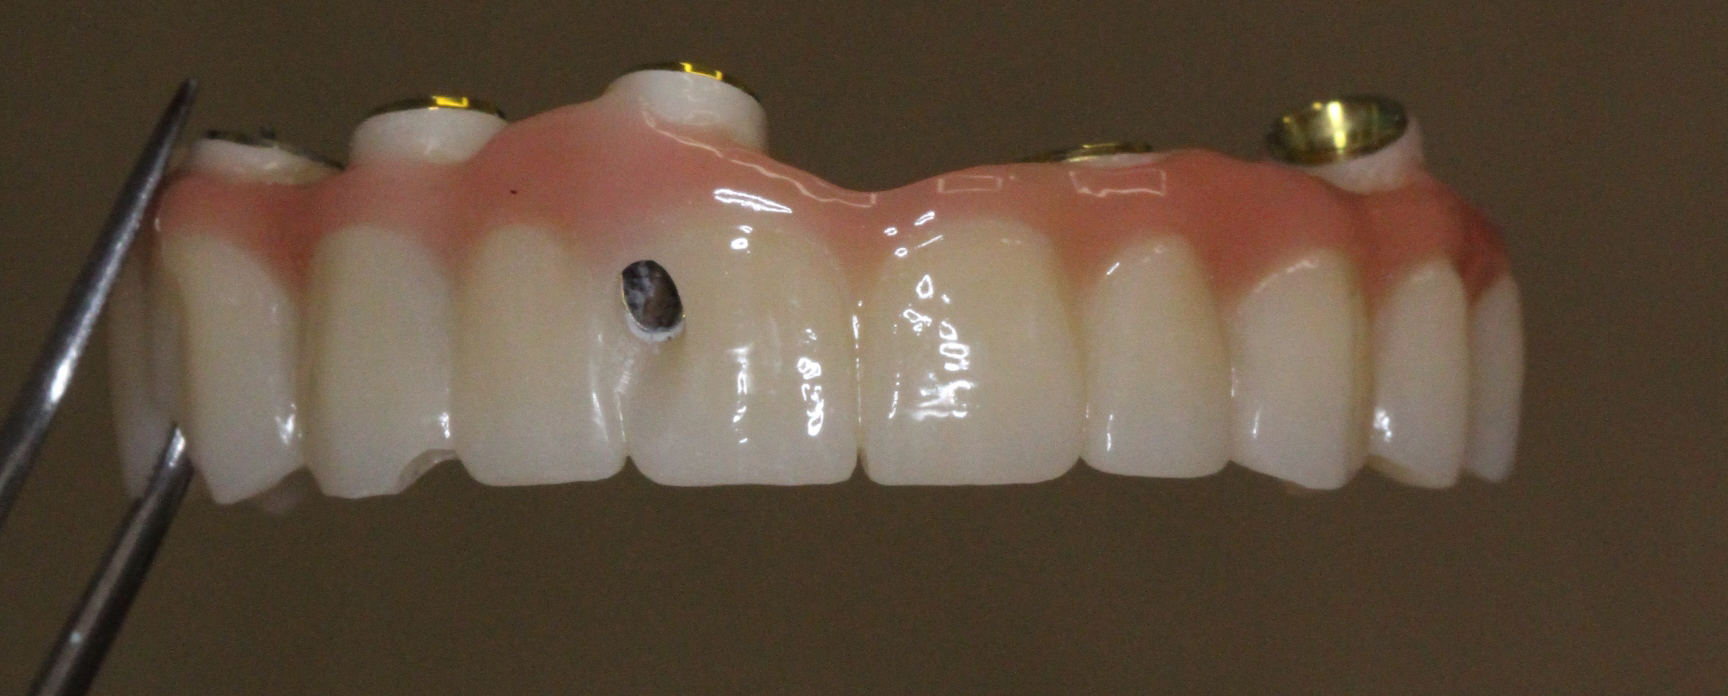

Two weeks later, the patient received her FP2 suprastructure, which was mounted using prosthetic screws. The screw access openings were sealed with composite, and custom-made zirconia posts were placed where visible for optimal esthetics.